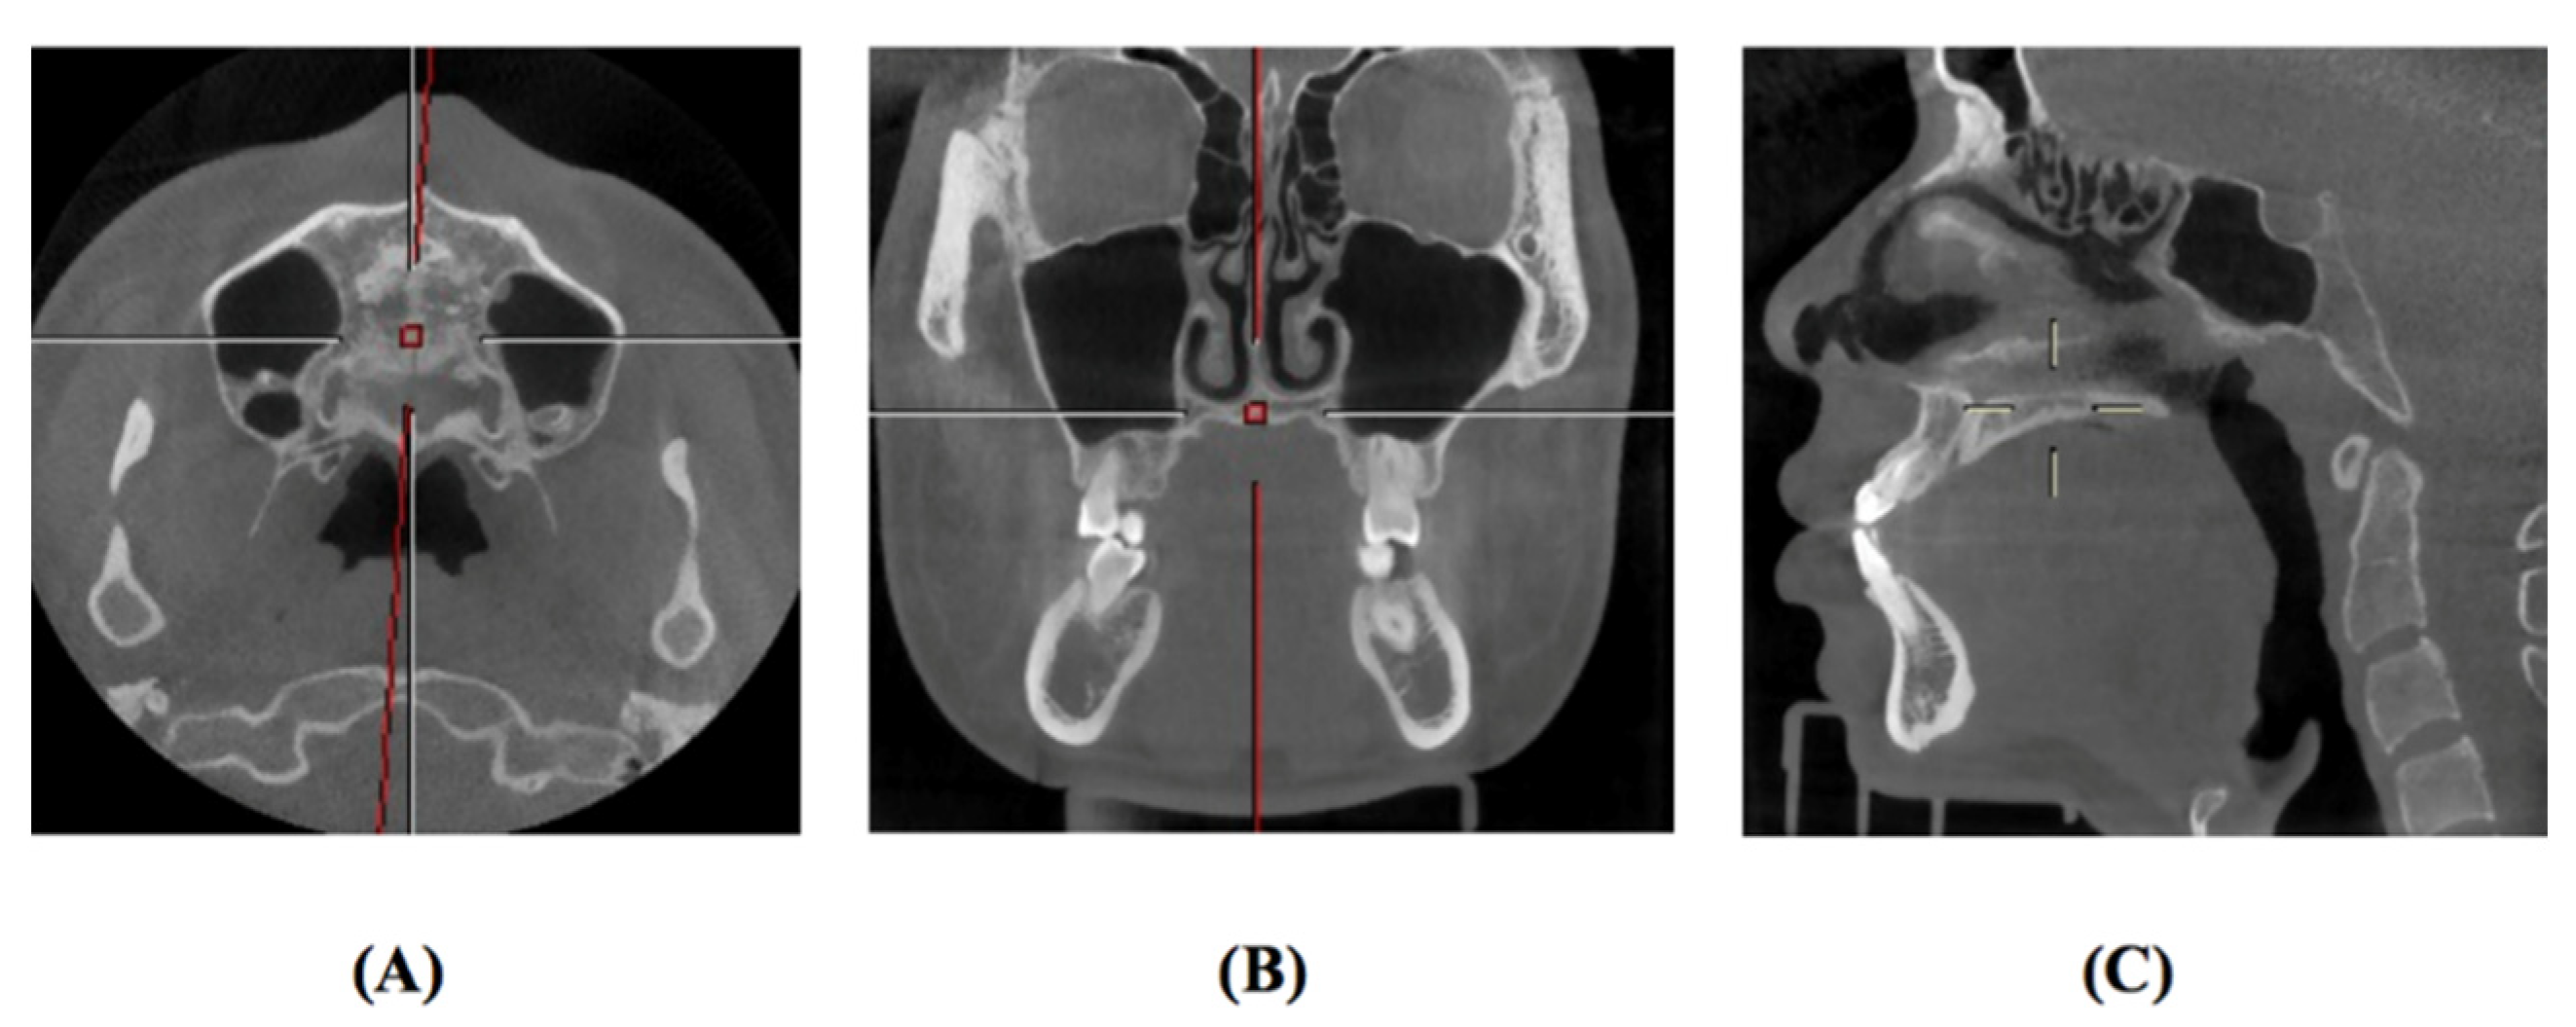

2.2. Region of Interest Labeling in Midpalatal Suture CBCT Images

3.2. Midpalatal Suture ROI Extraction and Image Fusion Algorithm